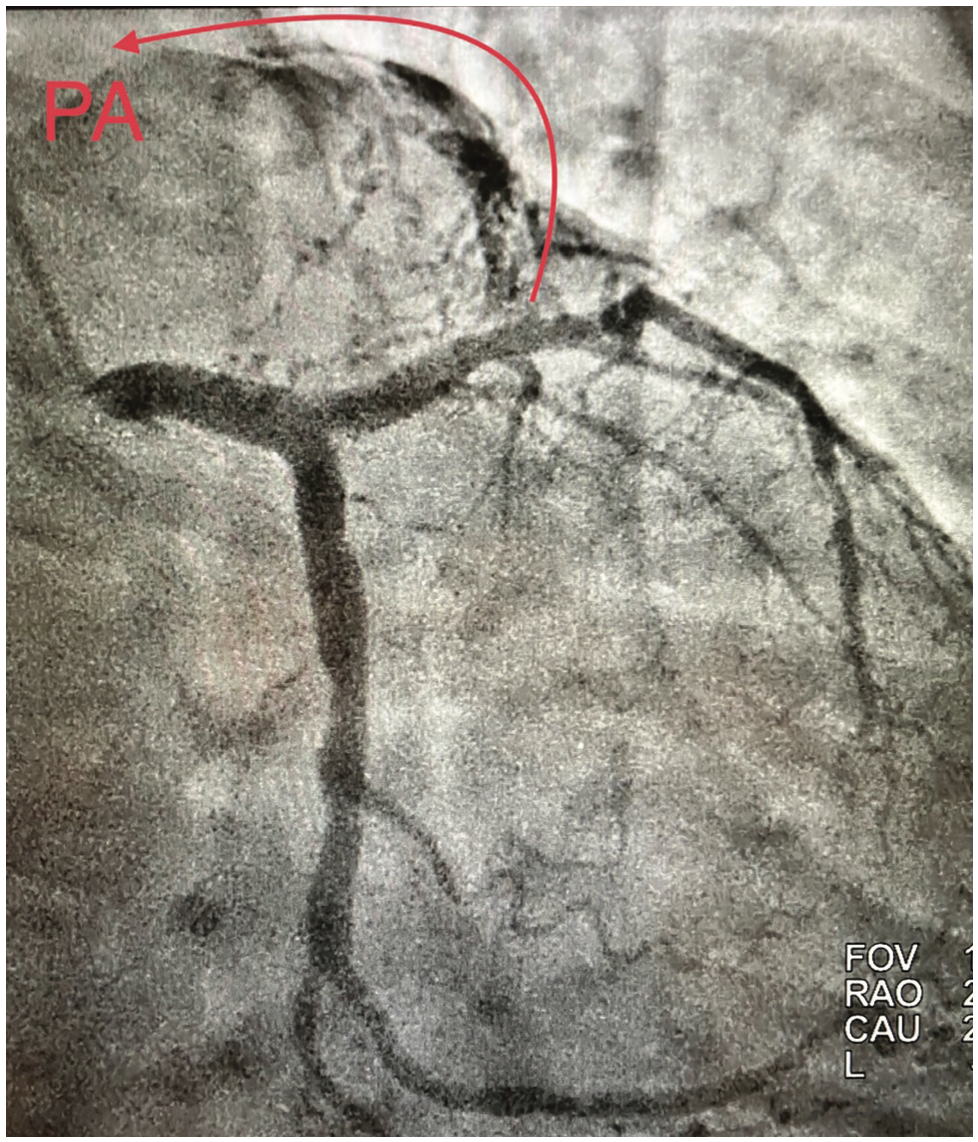

An important implication of this finding, however, was not discussed, likely due to space considerations. The authors show a fairly typical left anterior descending (LAD) to pulmonary artery (PA) fistula, but very interestingly, a conus to PA fistula. If the images could be superimposed, a perfect demonstration of Vieussens’ Ring would be observed. I have previously reported on this implication (see references), but I think that this case report is the clearest demonstration I have seen that proves the point of the likely embryologic origin of the coronary arteries.

Coronary artery to PA fistulae are a manifestation of the coronary buds arising in the truncus arteriosus and instead of septating into the aorta, instead become partitioned into the pulmonary artery. What is important is that they don’t seem to directly connect to the coronary, but rather form a ring shape, seen as a half ring in my case reports and as a wonderfully complete circle in the case report in CLD. The origin from the conus branch also shows the embryologic origin, as in the embryo there are actually 3 coronary arteries, but the third or conus vessel diminishes, and becomes either a right coronary artery (RCA) branch or a vestigial separate ostium.

What these images demonstrate is a re-emergence of Vieussens’ Ring through collateral development when coronary stenoses distal to the branch point increase in severity, causing an increase in flow through this vestigial channel. Indeed, collateral vessels generally are not due to neovascularization but rather arterialization of sinusoidal channels from the embryologic state which re-open with favorable hemodynamic forces.